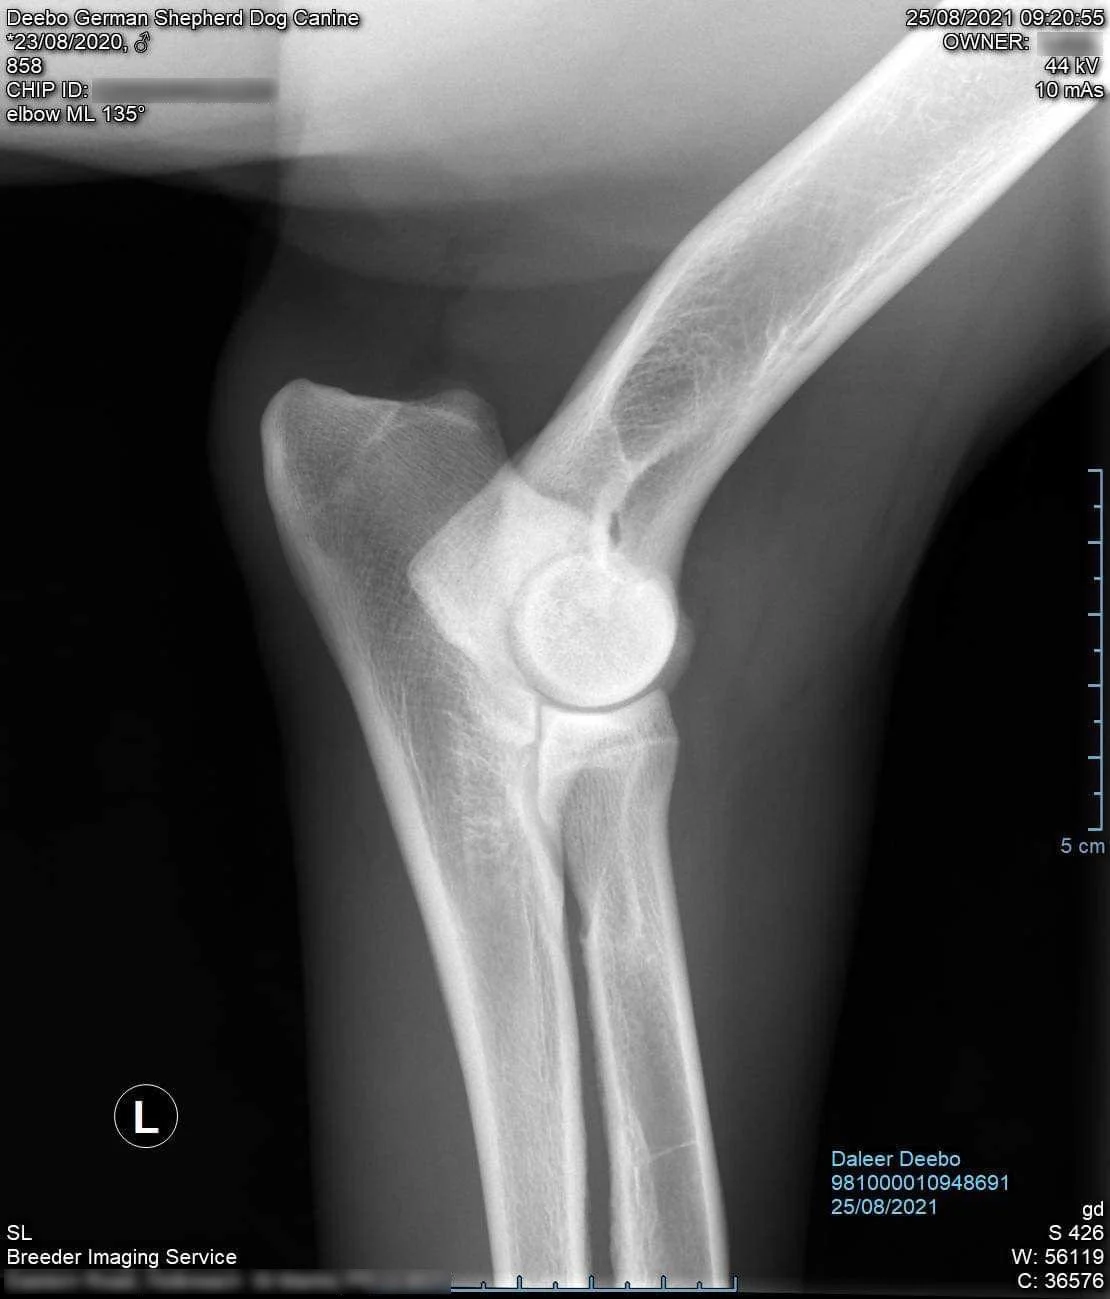

Health: HD/ED - SV Fast normal, normal, LUW-O